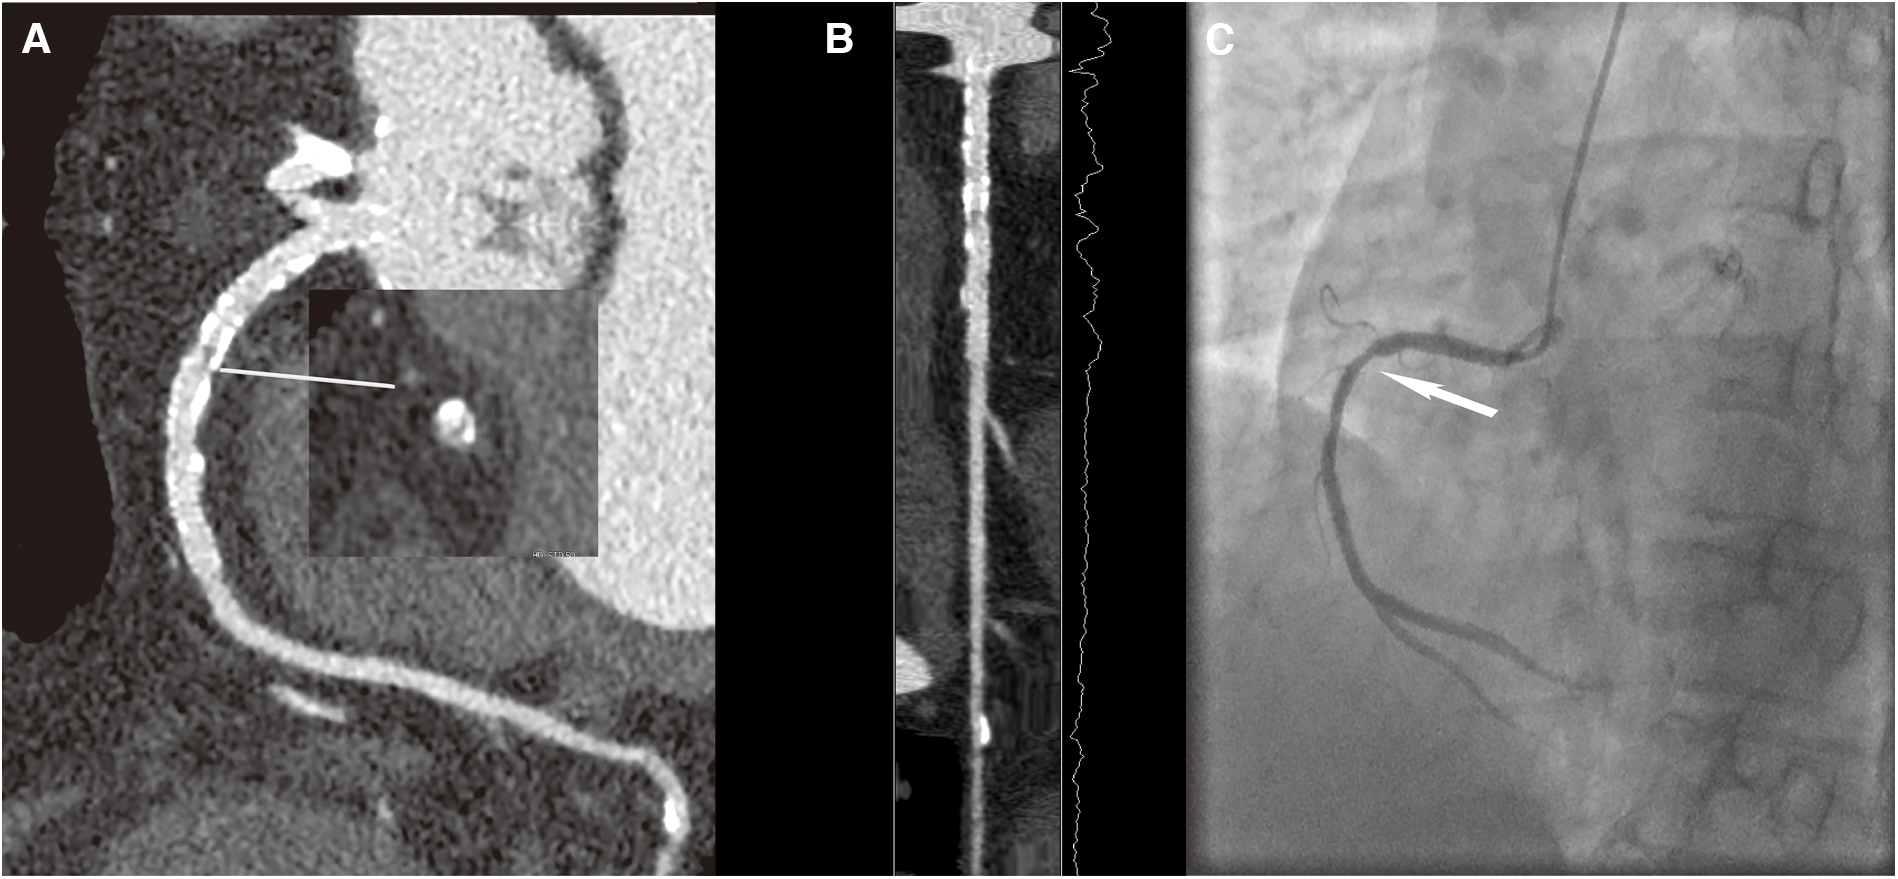

Figure 4

A 70-year-old female patient with ISR in the HD group, with a BMI of 26.4 kg/m2. (A) The image quality reached a subjective score of 4 with minimal stent margin definition, some blooming artifacts, acceptable diagnostic information, and an image noise of 35 HU. (B) CPR image of RCA showed focal ISR in a 3.0 mm coronary stent (resolute 3.0 × 33 mm, Firebird). (C) ICA of the right coronary artery confirmed the diagnosis of focal ISR (white arrow).